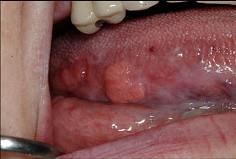

以下关于舌癌(如图)的叙述,哪项是错误的 ( )

A舌根部癌可向茎突后及咽后部的淋巴转移

B以鳞状细胞癌多见

C转移途径多为直接浸润和种植转移

D常发生早期颈部淋巴结转移

E多发生于舌缘,恶性程度高